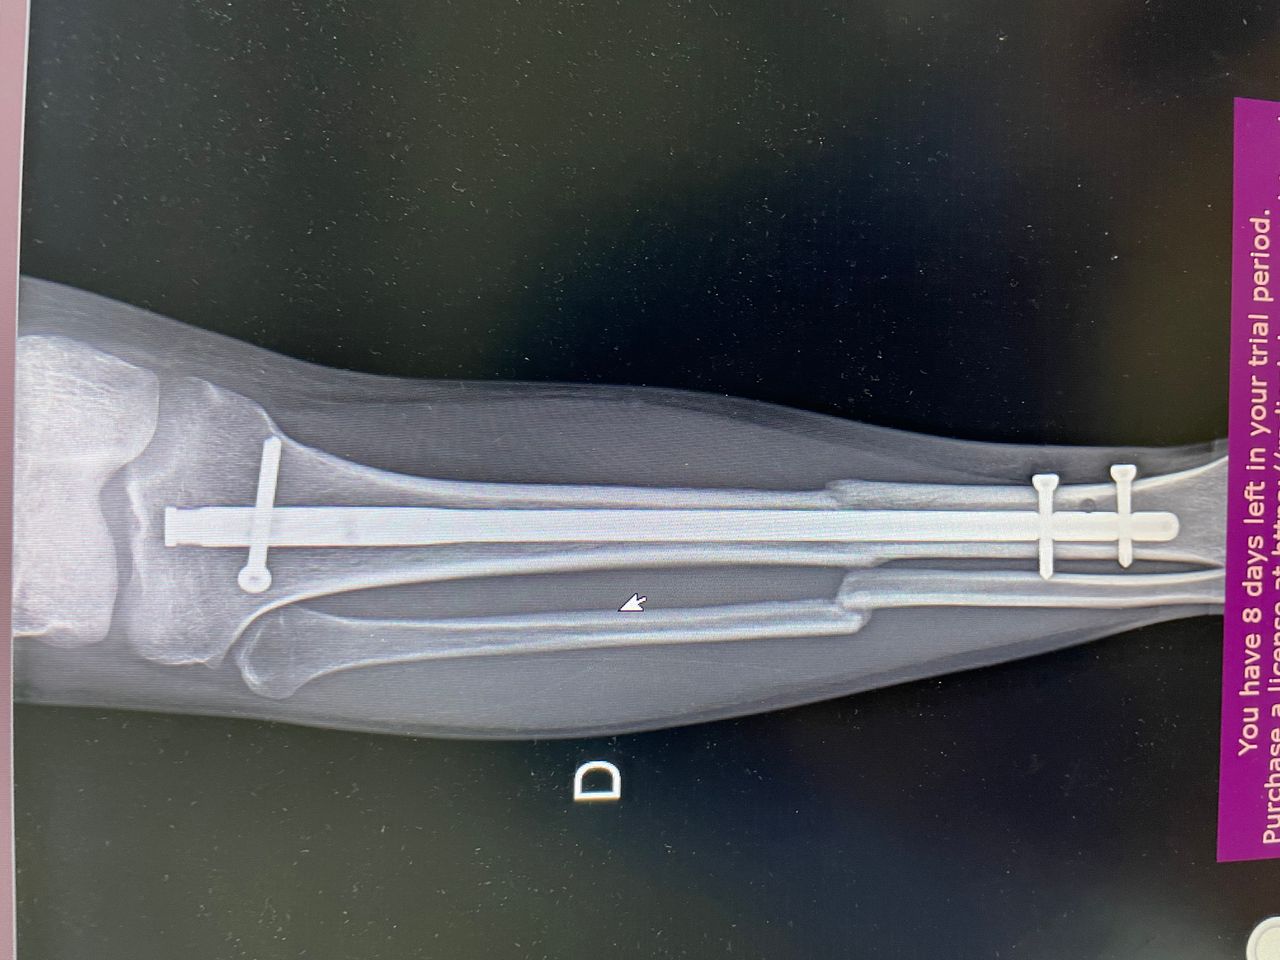

Fotos y videos

El doctor tiene mucha experiencia, muy buena atención y la ayuda de la toma de placas excelente.